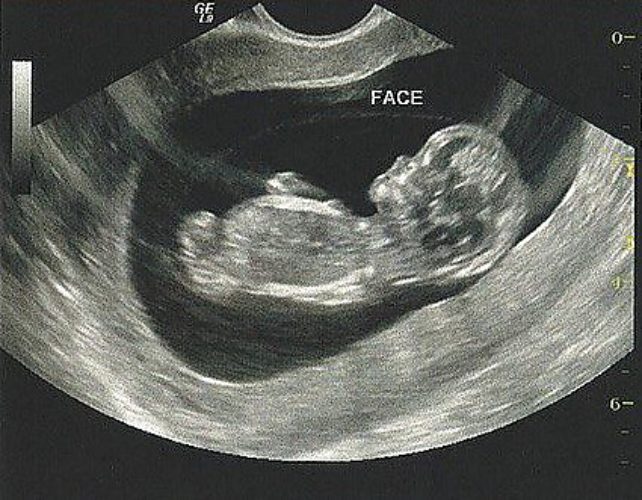

11 недель зачатия